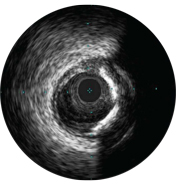

IVUS can help clarify degree and type of stenosis (i.e, MLA, plaque burden, and calcium). While IVUS can also characterize plaque rupture, thrombus, and dissection, calcium may be more common in everyday PCI. An important factor in your stenting strategy, calcium is characterized by very bright areas with acoustic shadowing that blocks out the image behind. Reverberations may also be seen.

The incidence of edge dissection after DES implantation is reported to be 10%, with almost 40% of those undetected by angiography. A dissection angle ≥60° or MLA<4mm2 indicates a high grade dissection that should be treated. These characteristics are associated with higher rates of early stent thrombosis.2

Stent expansion is a predictor of stent thrombosis and restenosis. Target minimum stent areas post-PCI may include: ≥80% of the average reference lumen areas, 6 mm2 for DES in non-LM vessels, or other criteria depending on the type of PCI. IVUS helps document your result.2